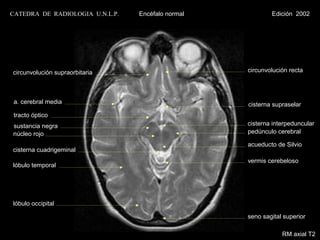

CATEDRA DE RADIOLOGIA U.N.L.P.   Encéfalo normal           Edición 2002

circunvolución supraorbitaria                      circunvolución recta

a. cerebral media                                  cisterna supraselar

tracto óptico

sustancia negra                                    cisterna interpeduncular

núcleo rojo                                        pedúnculo cerebral

acueducto de Silvio

cisterna cuadrigeminal

vermis cerebeloso

lóbulo temporal

lóbulo occipital

seno sagital superior

RM axial T2